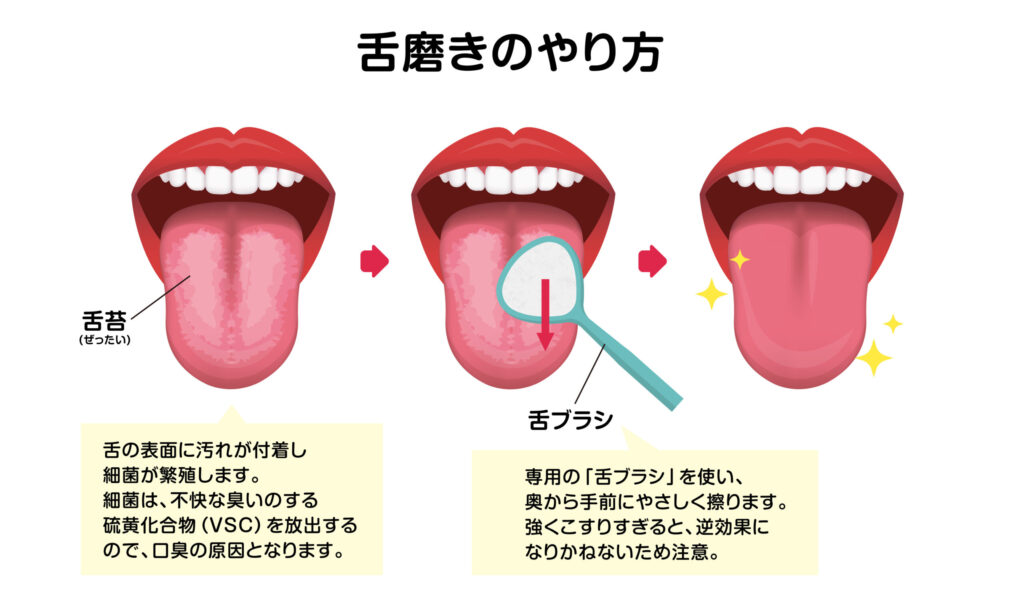

舌の苔をとってはいけない人の話。養生法と漢方植松光子。